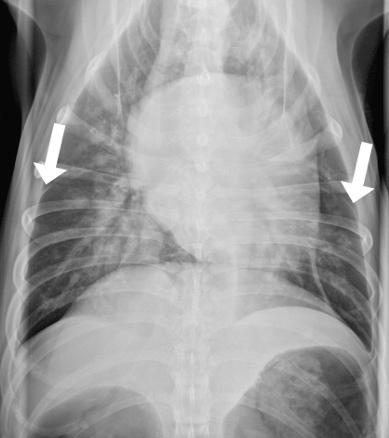

![]() | Pleural thickning - Plueral fissure line - 흉막염(훙막벽이 두꺼워지거나 염증이 생길 때)도 생길 수 있음 (5%) - 보통은 흉수 때문(95%) |

![]() | Pleural effusion - 물이 차서 심장이 안 보이고 폐가 들려 있고 끝이 뭉툭. - tracheal elevation - 흉수 뽑고 다시 찍어봐야 함. |